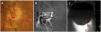

Utilidad de la ecografía ocular en el tratamiento fibrinolítico de la oclusión de la arteria central de la retina

Utility of ocular ultrasonography in the thrombolytic therapy for acute central retinal artery occlusion

Figuras (1)